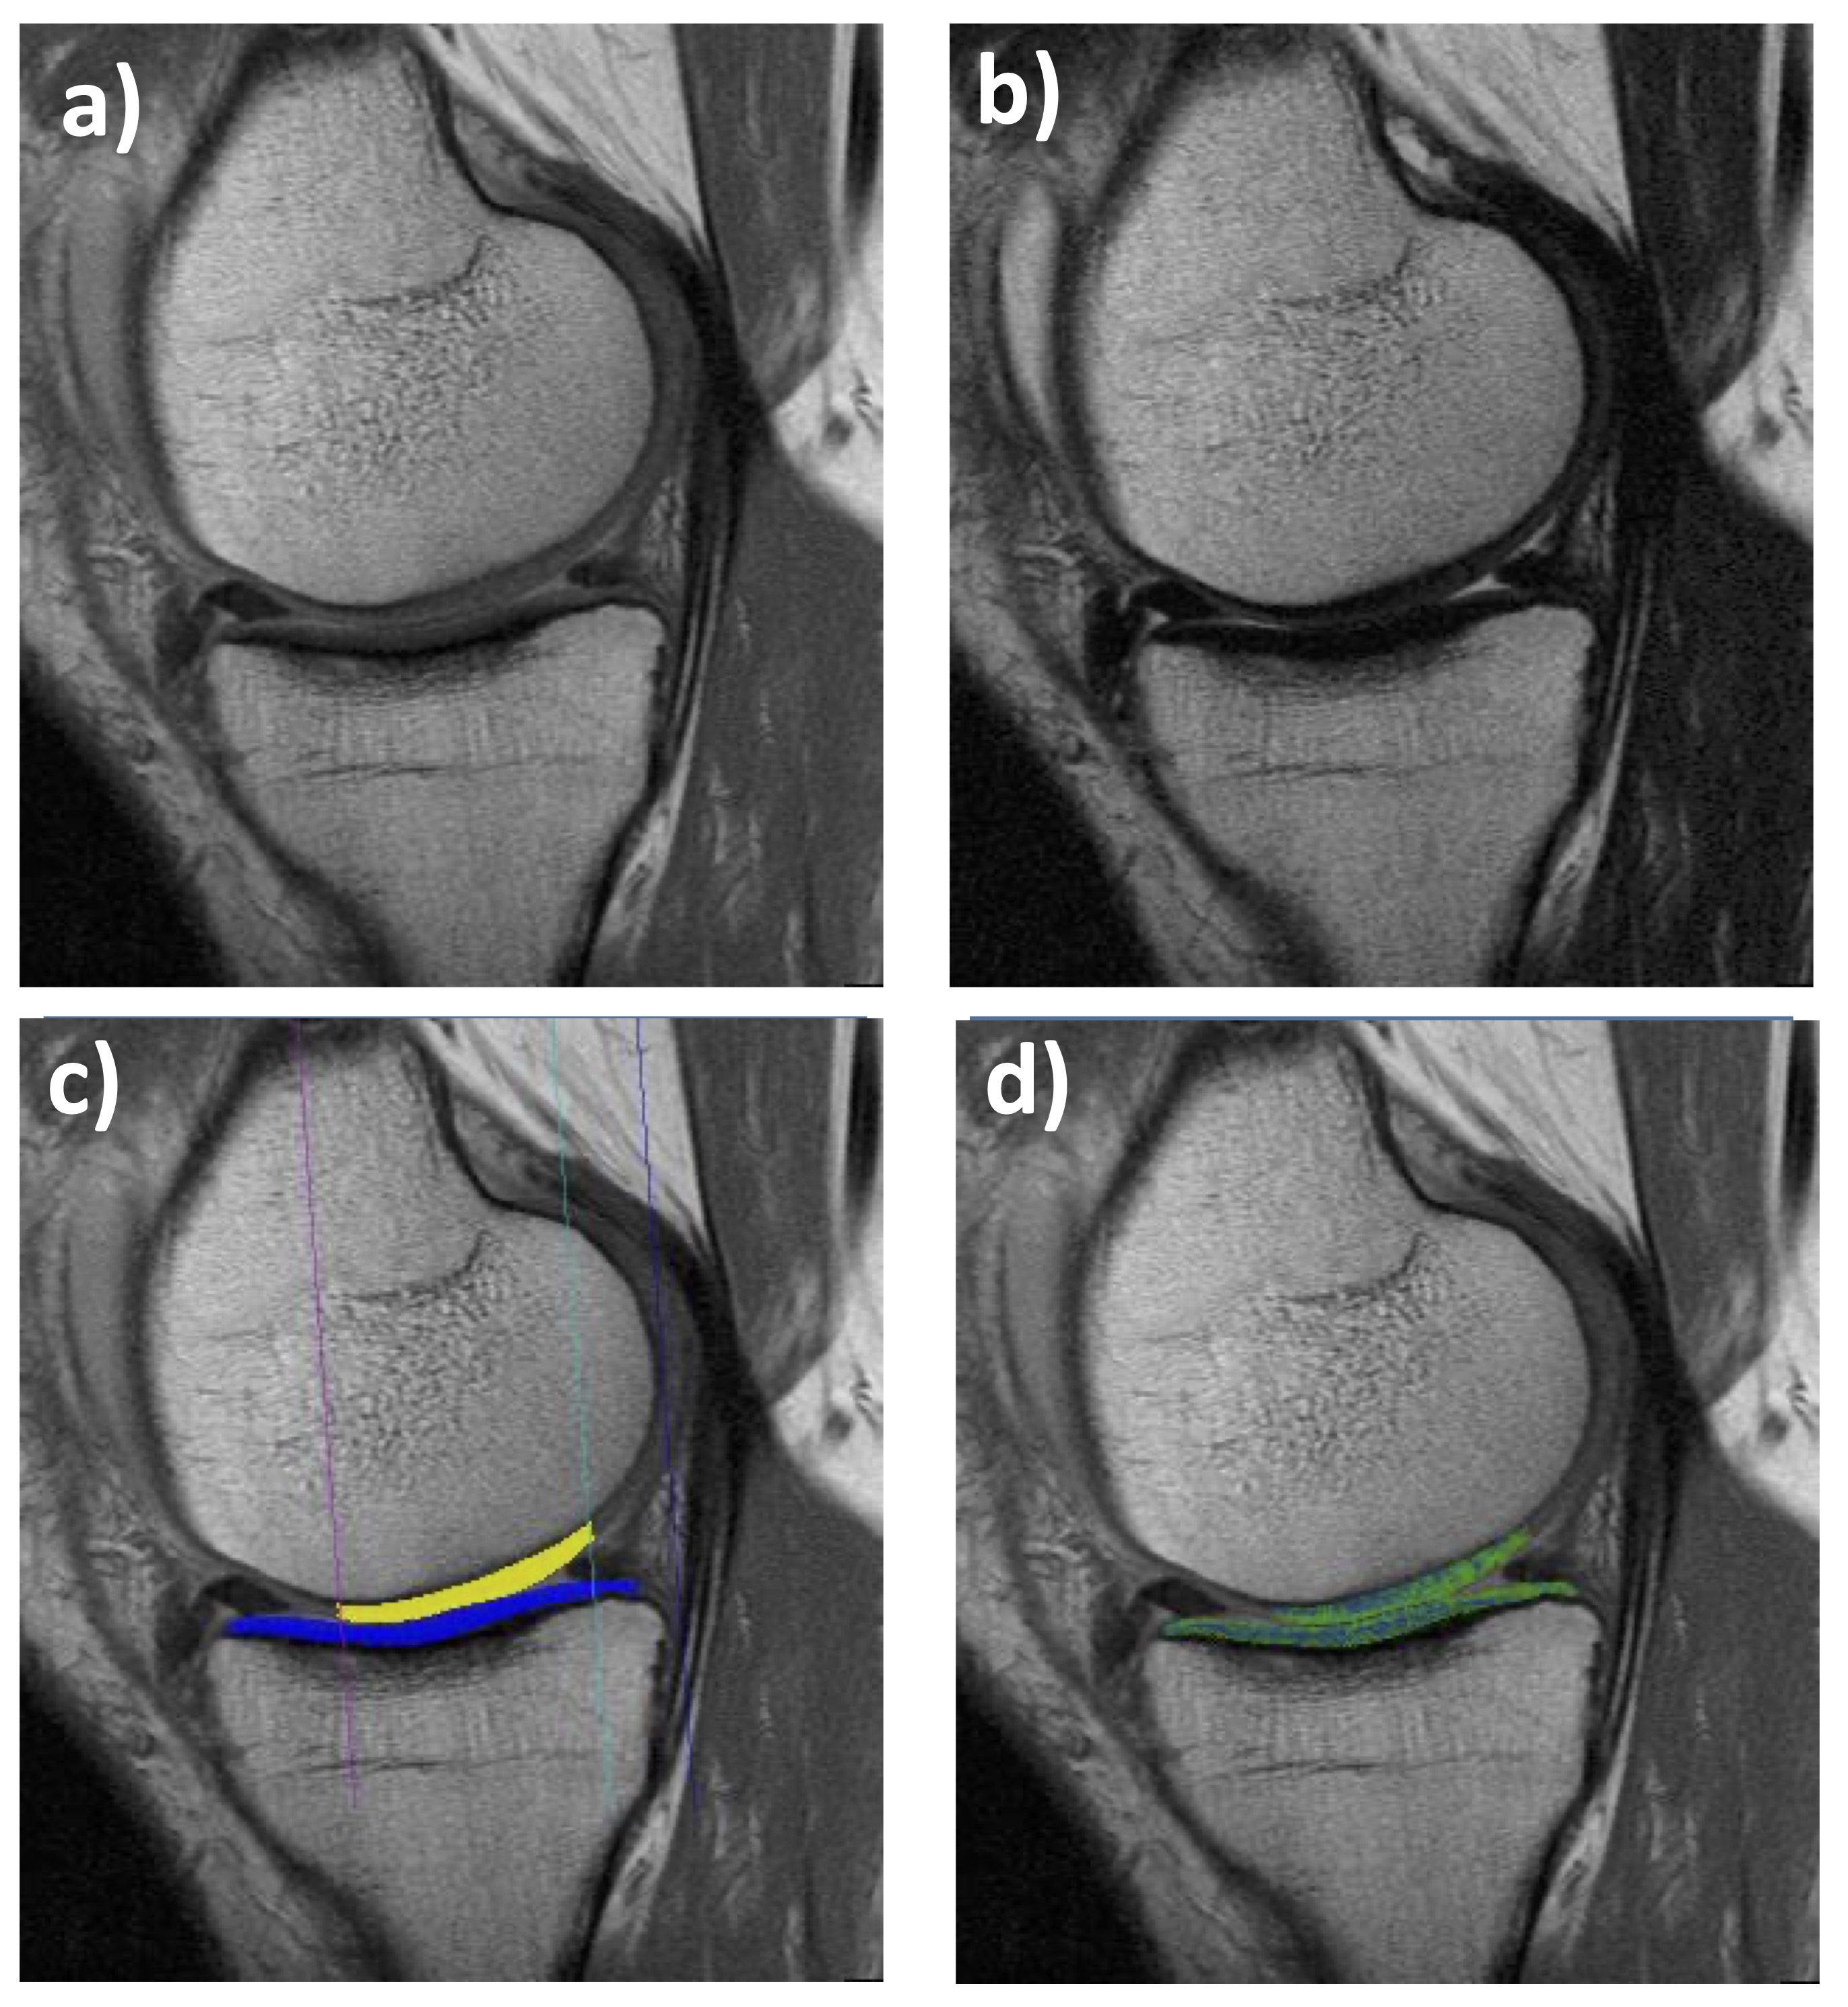

Figure 1. Sagittal multiple-echo spin-echo (MESE) MRI of the medial femorotibial compartment (MFTC): a) Shortest echo (10 ms); b) Longest echo (70 ms); c) Cartilage segmentation of the medial tibia (MT) and lateral tibia (LT); d)T2 map (only cartilage T2 is shown, no other structures)

From an MR image acquisition perspective, T2 maps can be generated by various spin echo or gradient echo techniques [4]; the most widely used is 2D multiple-echo spin-echo (MESE – Fig. 1). MESE uses 4-8 different echo times (TEs) to derive T2 on a voxel-by-voxel basis. Yet a more versatile 3D gradient echo-based sequence has recently been proposed, i.e. quantitative double echo at steady state (qDESS – Fig. 2) in combination with water excitation [23–28]. qDESS generates two echoes per repetition time (Fig. 2), separated by a spoiler gradient. An image is formed from each echo, and T2 can then be computed from changes in voxel signal intensity between the two sets of images. The image formed from the first echo displays mixed T1/T2 contrast, whereas the image formed from the second echo exhibits contrast with contributions from both T2 and diffusion effects. Conventional DESS[24, 29, 30] combines data from both echoes (Figs 2 a, b) to generate a single (fused) image with mixed T1-/T2-contrast (Fig. 2c), enabling morphometry but not relaxometry (T2). However, with a modification of the gradient fields and images from both echoes stored separately (qDESS), a voxel-by-voxel fit can generate the desired high-resolution T2 map (Fig. 2f). This approach has been validated versus single echo spin echo T2, the gold standard for this type of measurement [23–27].